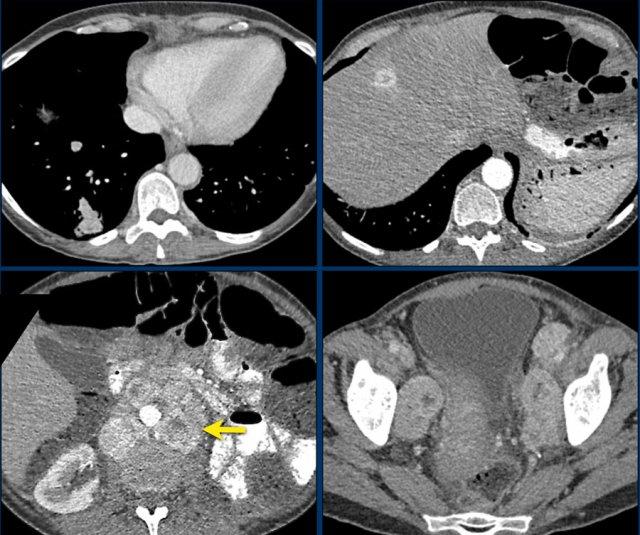

Hình ảnh thể hiện cửa sổ trung thất và cửa sổ xương của một bệnh nhân có khối u tuyến thượng thận phải kích thước lớn, ngấm thuốc không đồng nhất.

Khối u này đã được xác nhận là ung thư biểu mô vỏ thượng thận.

Có một tổn thương gan mờ nhạt, bờ không rõ ở phân thùy 6 và các thay đổi xơ cứng không đặc hiệu ở thân đốt sống T12.

Tiếp tục xem hình ảnh PET…

PET-CT thực hiện để phân giai đoạn toàn diện cho thấy sự hấp thu mạnh tại khối u tuyến thượng thận, gợi ý bản chất ác tính của khối u.

Ngoài ra còn ghi nhận sự hấp thu mạnh tại hai ổ di căn gan và một ổ di căn xương ở T12.

Khoảng 20-40% bệnh nhân ung thư biểu mô vỏ thượng thận đã có di căn tại thời điểm chẩn đoán.